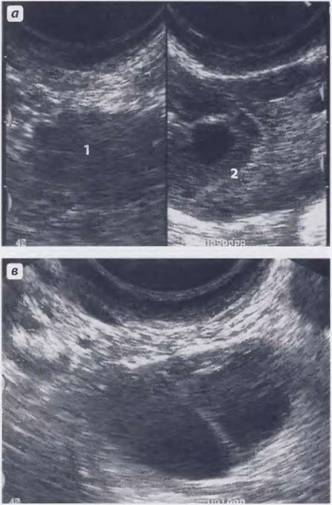

Эти образования хорошо визуализируются при проведении ультразвукового исследования или магнитно-резонансной томографии. Однако во время УЗИ невозможно увидеть ткани, из которых состоит образование, поэтому можно лишь предполагать наличие кальцината. Такая ситуация требует дополнительного обследования женщины, чтобы исключить более серьезные заболевания, чем просто наличие отложений солей кальция.

- трансвагинальное УЗИ, которое обеспечивает более детальное исследование органа, особенно в период беременности;

- трехмерное УЗИ – современный метод диагностики заболеваний матки, который позволяет визуализировать кальцинаты в трехмерном формате;

На сегодняшний день трехмерное УЗИ считается самым точным методом диагностики заболеваний матки, однако его стоимость значительно выше по сравнению с другими методами.